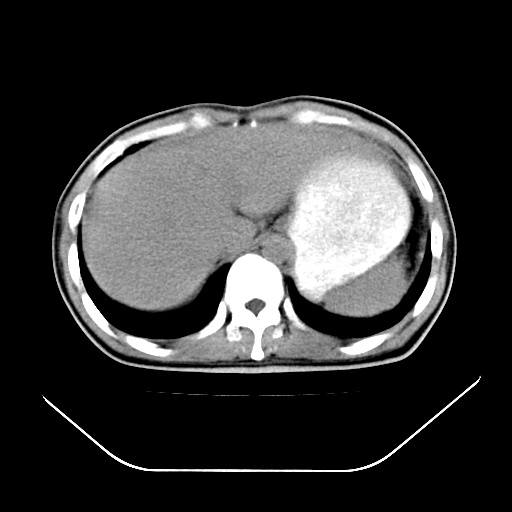

以下是引用深泽交通医院在2008-7-17 12:05:00的发言:[br]肝门淋巴结肿大;胆结石

以下是引用文莱在2008-7-17 16:32:00的发言:[br]胆囊结石 余未见异常

以下是引用随光逐影在2008-7-17 17:52:00的发言:[br]1)胆囊结石。2)肝门及胰头区淋巴结肿大可能(原因不明);建议行进一步检查。

以下是引用卜一在2008-7-17 16:37:00的发言:[br]支持胆囊结石!!!至于胰头区病变——建议强化后再定论!